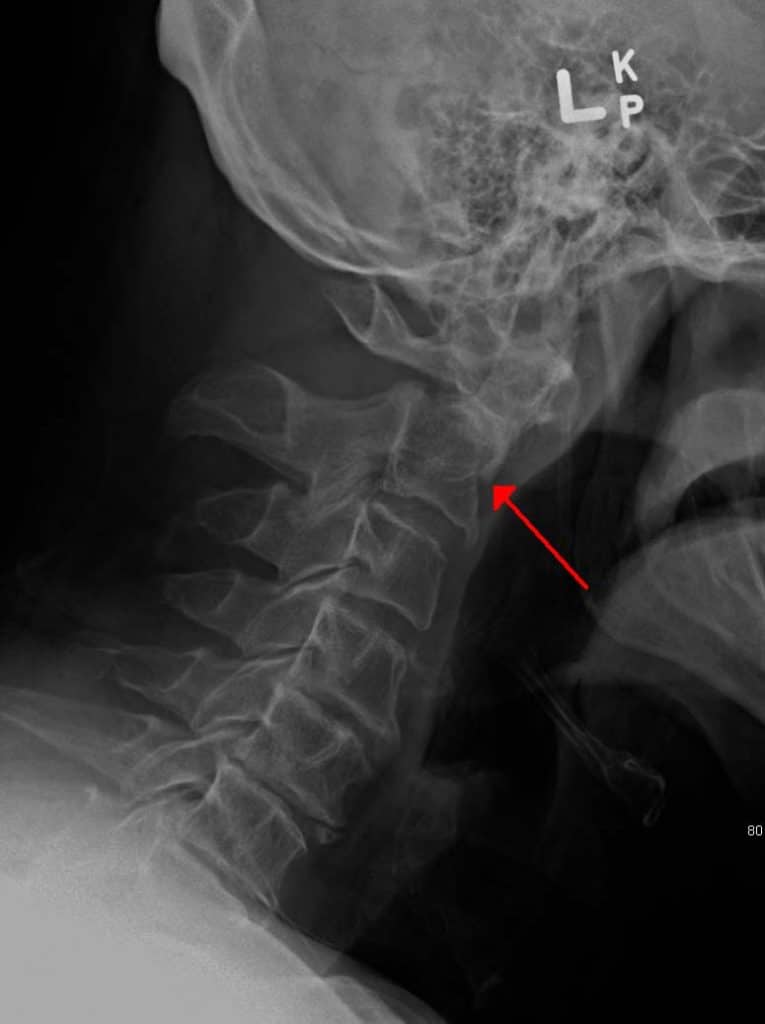

Fracture of the Dens

Fractures of the odontoid process represent ~40% of C2 fractures.

Often these fractures are unstable and are at high risk of avascular necrosis – due to the isolation of the distal fragment from any blood supply.  As with any fracture of the vertebral column, there is a risk of spinal cord involvement.

1.4 - A fracture of the base of the dens.

Fig 6

A fracture of the base of the dens.